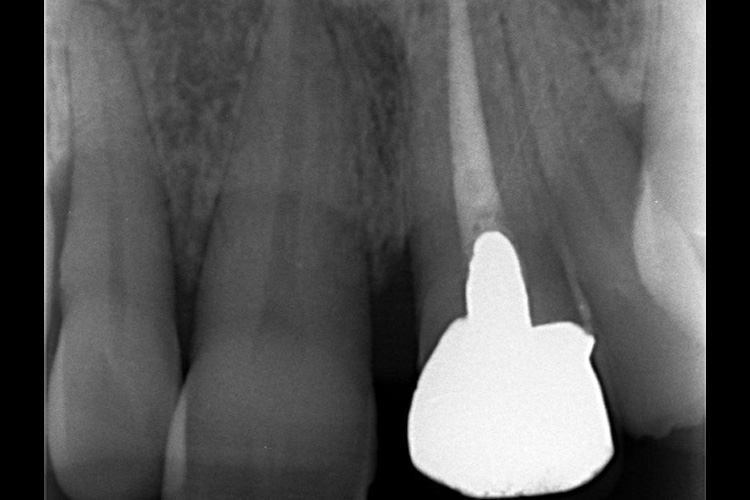

この患者様は、口腔内全体において重度の歯周病が生じており、歯磨き指導、クリーニング、Flap手術等を行ったが、歯周ポケットが深すぎるためブルーラジカル適用症例と診断し、施術を行いました。

実施前

施術前のレントゲンと口腔内写真です。施術前にプラークの除去を行ってから、施術します。